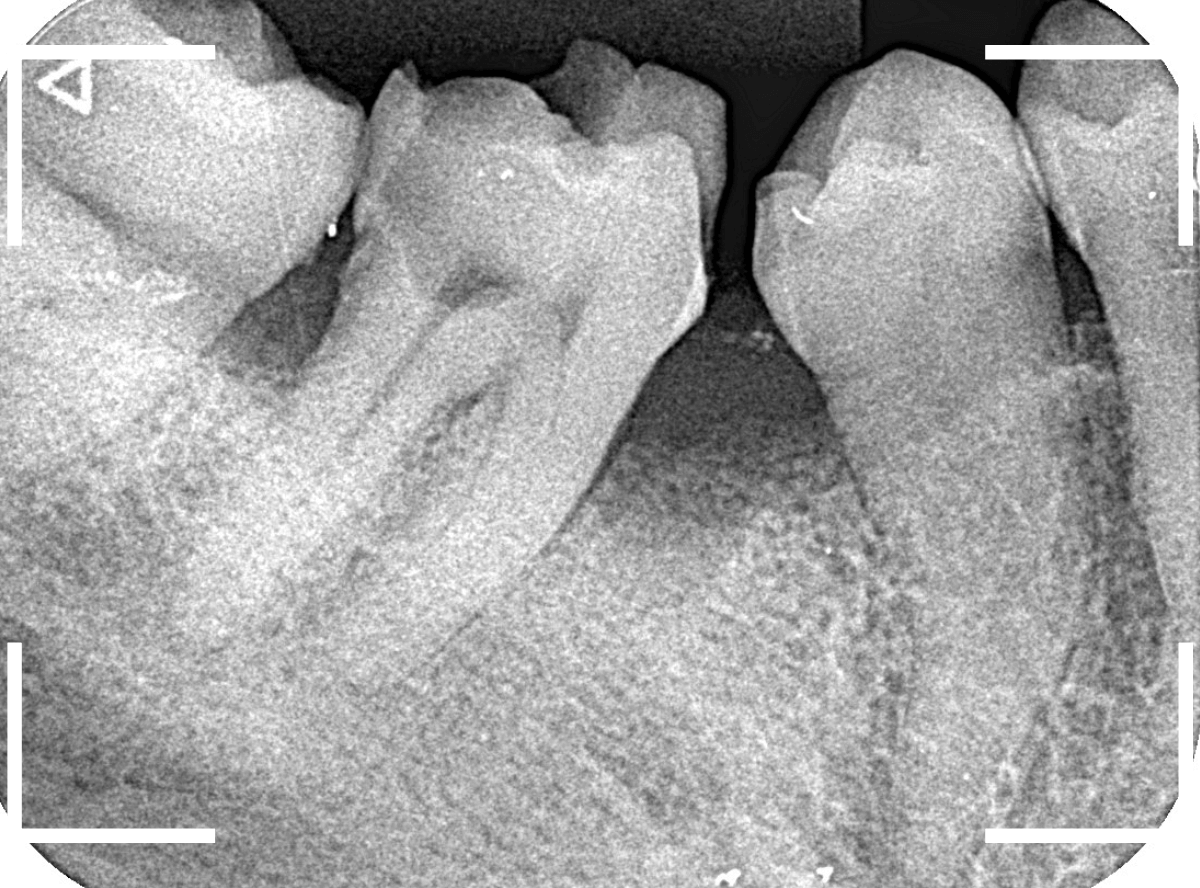

Case.15 レジンの下の深い虫歯

奥歯で咬んだ時に、痛みを感じるという訴えで来院された患者さんです。

パッと見は特に問題なさそうな状態ですが、大きなレジン治療がしてあり、レジンの奥もボヤっと黒っぽく見えてアヤシイ感じです。

レントゲン写真で確認します。

青い線が神経、赤い線が虫歯です。

神経に触ってしまいそうなほどの大きな虫歯です。

(隣の歯も虫歯がありそうです)